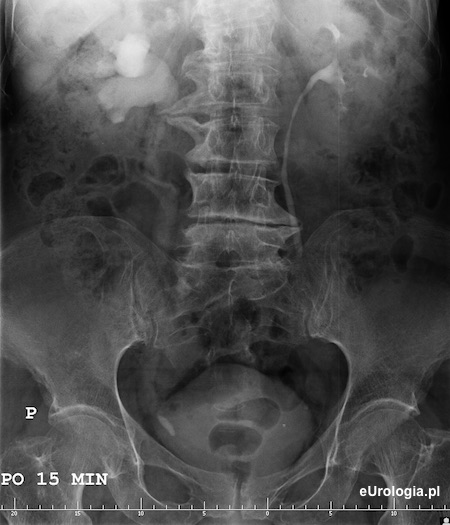

Wodonerczowato poszerzony UKM prawej nerki i moczowód prawy aż do opisywanego cienia - złóg w dolnym odcinku prawego moczowodu